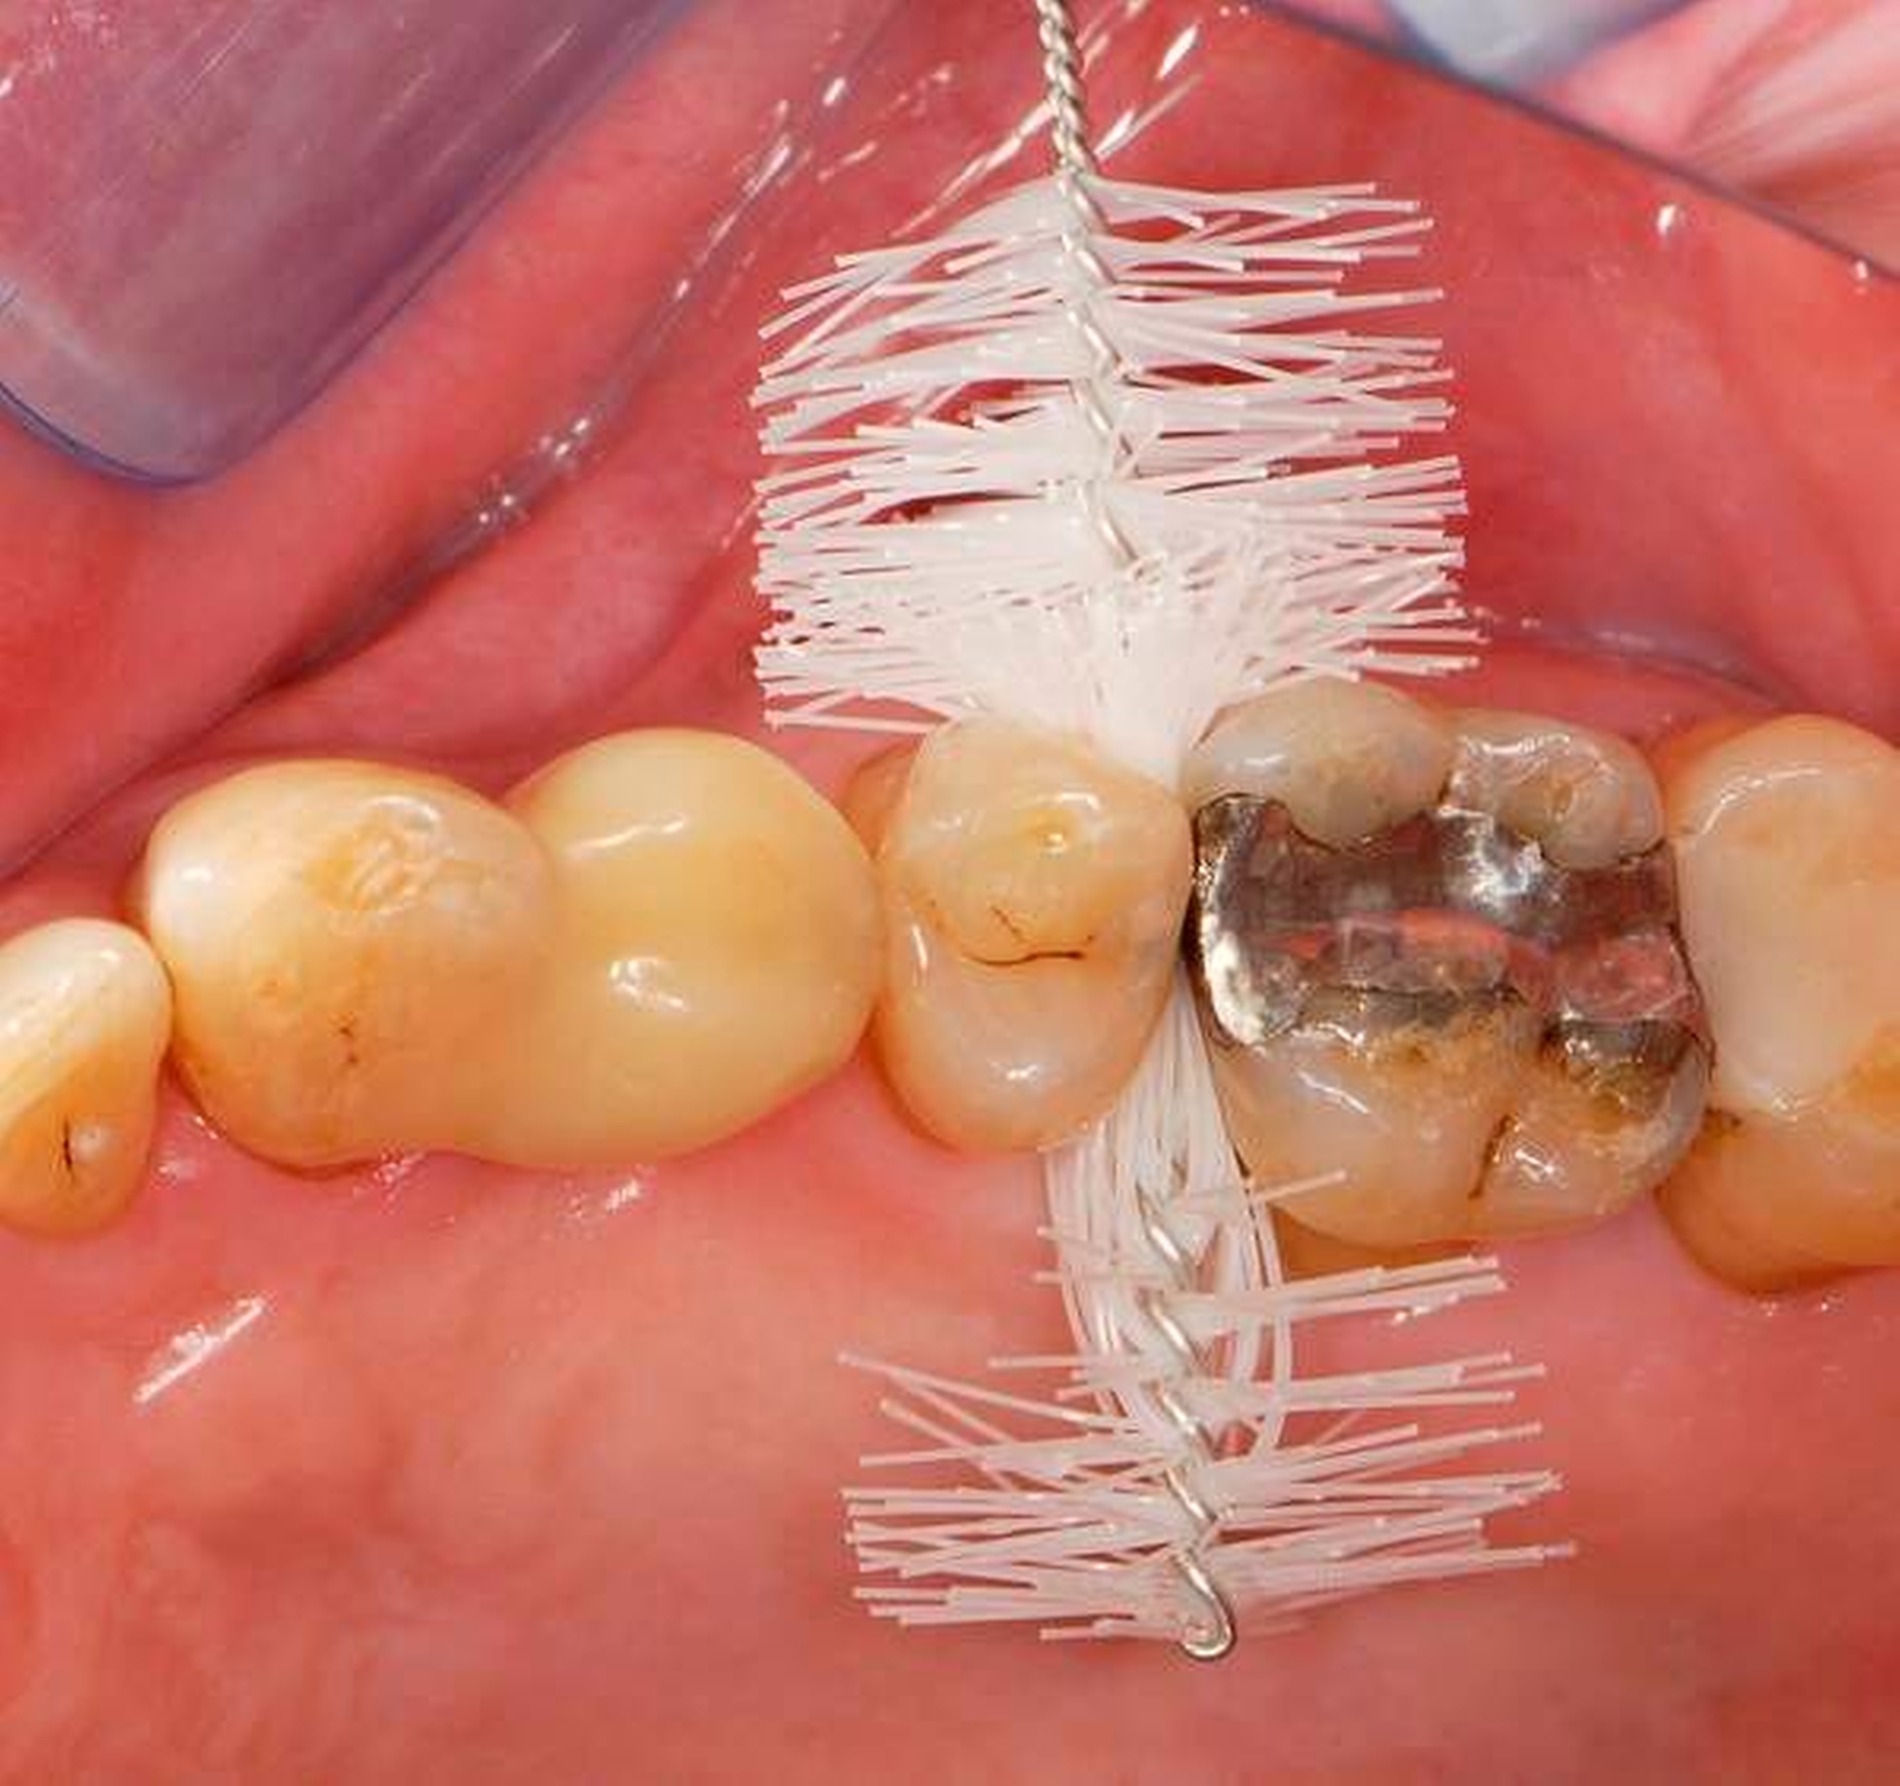

Abbildung 3: Direkte Reparatur im Seitenzahnbereich (R2-Technik)

In den Abbildungen 1 bis 3 werden Optionen für frugale Interventionen auf restaurativem Sektor aufgeführt. Es handelt sich um direkte Vollüberkronungen im Frontzahnbereich (hier: hergestellt in R1-Technik / einphasig) (Abbildung 1), direkte Teilüberkronungen im Seitenzahnbereich (hier: hergestellt in R1-Technik / einphasig) (Abbildung 2), Reparatur-Restaurationen im Seitenzahnbereich (hier: hergestellt in R2-Technik / zweiphasig) (Abbildung 3). Technische Einzelheiten zur Vorgehensweise und den Ergebnissen sind an anderer Stelle beschrieben (Literatur siehe oben).

schadensgerechte Reparaturtechniken (Abbildung 3),